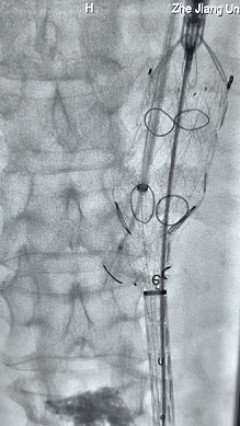

3. 经右股动脉导入超硬导丝,然后导入先健G-Branch 胸腹主动脉主体覆膜支架TAAA3418120e7i1010 一枚,释放主体支架至内分支打开,然后经左侧肱动脉入路,抓捕预置导丝成功后,将长鞘进入内分支出口处。

4. 经长鞘导入导管后,超选入腹腔干动脉,送入先健覆膜支架10*80mm一枚,近端重叠内分支,远端重叠腹腔干动脉,并予以10mm球囊后扩,手推造影显影良好。

5. 撤出腹腔干导丝导管,经左肱动脉长鞘继续抓捕预置导丝将长鞘超选至另一侧内分支,后超选进肠系膜上动脉,沿导丝送入先健覆膜支架10*100mm一枚,近端重叠内分支,远端重叠于肠系膜上动脉,并予以10mm球囊后扩,手推造影显影良好。

6. 解除束径,打开近端后释放,经肱动脉长鞘超选支架外分支,并进一步超选右侧肾动脉,交换加硬导丝,送入覆膜支架6*50mm和7*60mm各一枚,并予以球囊后扩张,手推造影显影良好。

7. 经长鞘重新选入左侧外分支,并超选进左肾动脉,沿导丝送入外周血管覆膜支架7*60mm一枚,并予以球囊后扩张,手推造影显影良好。